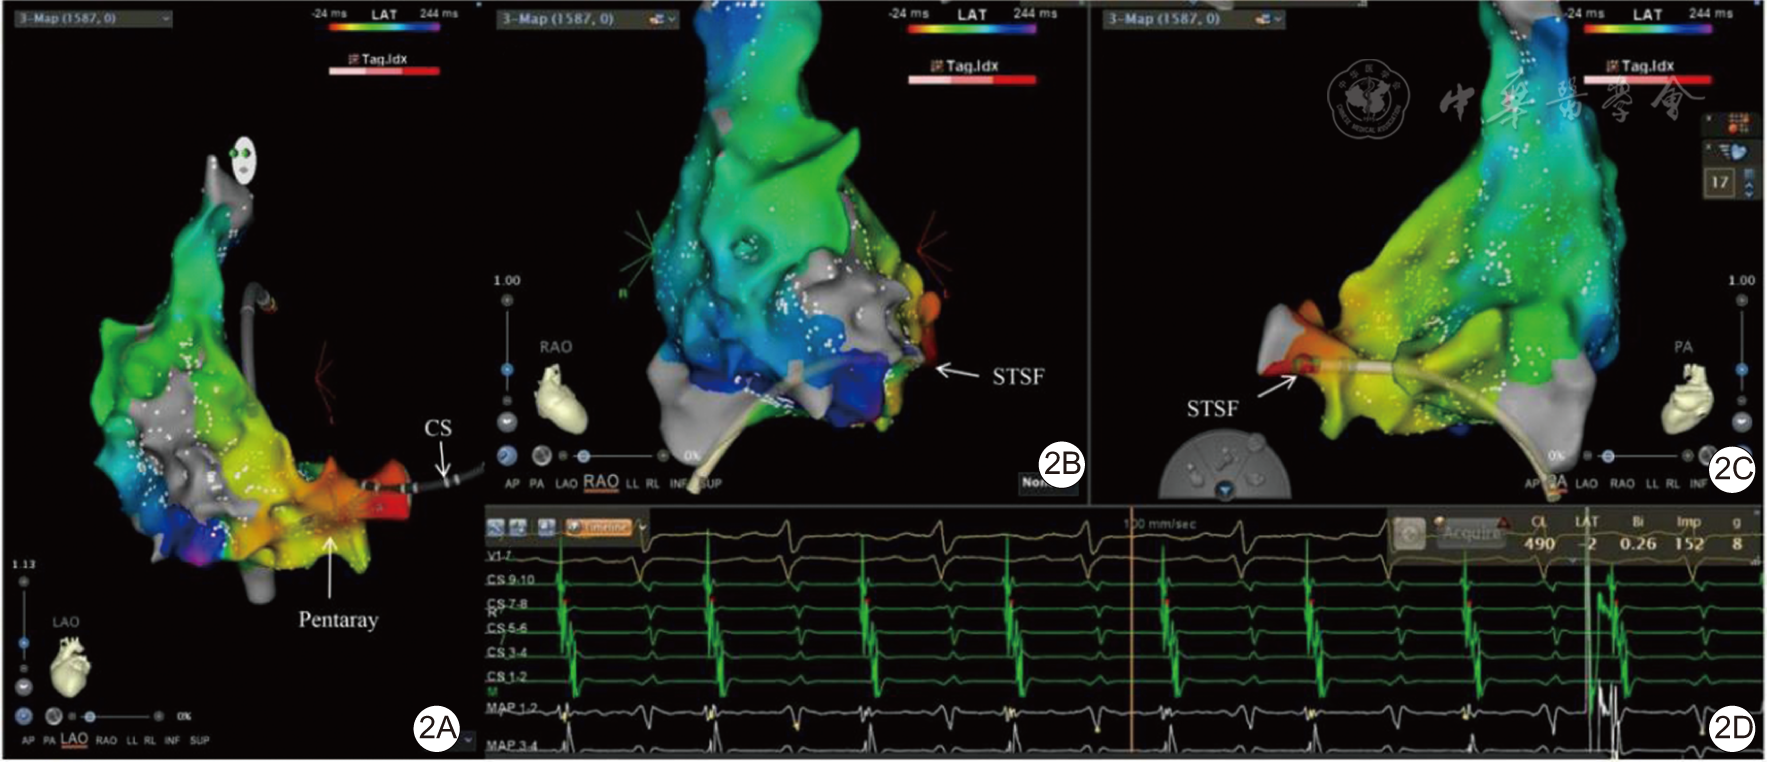

图2 患者房性心动过速(房速)激动标测图及腔内电图[2A为右心房激动标测图(右前斜30°),可见游离壁中部存在瘢痕,图中显示为白色条状;2B为右心房激动标测图(左前斜45°),可见房速围绕三尖瓣环逆钟向折返;2C为房速时体表心电图及腔内电图(纸速100 mm/s),从上到下依次为体表I、Ⅱ、V1导联、CS 90至CS 12、Pentaray 1-2至Pentaray 19-20,房速周长302 ms,呈房室2∶1下传;2D为右心房激动标测图(右前斜30°、足位),可见房速同时存在围绕瘢痕的顺钟向折返。黄色点代表His,白色点代表三尖瓣瓣环]His为希氏束,CS为冠状静脉窦